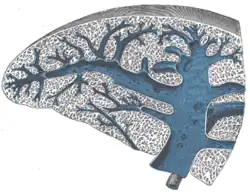

Secção transversa do baço, mostrando seu tecido trabecular, a veia esplênica e suas tributárias.

Secção transversa do baço, mostrando a distribuição da artéria esplênica e seus ramos.

Secção do baço, mostrando a terminação dos pequenos vasos sanguíneos.